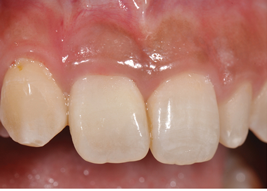

(19.) Preoperative view of a failing central incisor (tooth No. 9). Note the early recession occurring in the region.

Figure 19